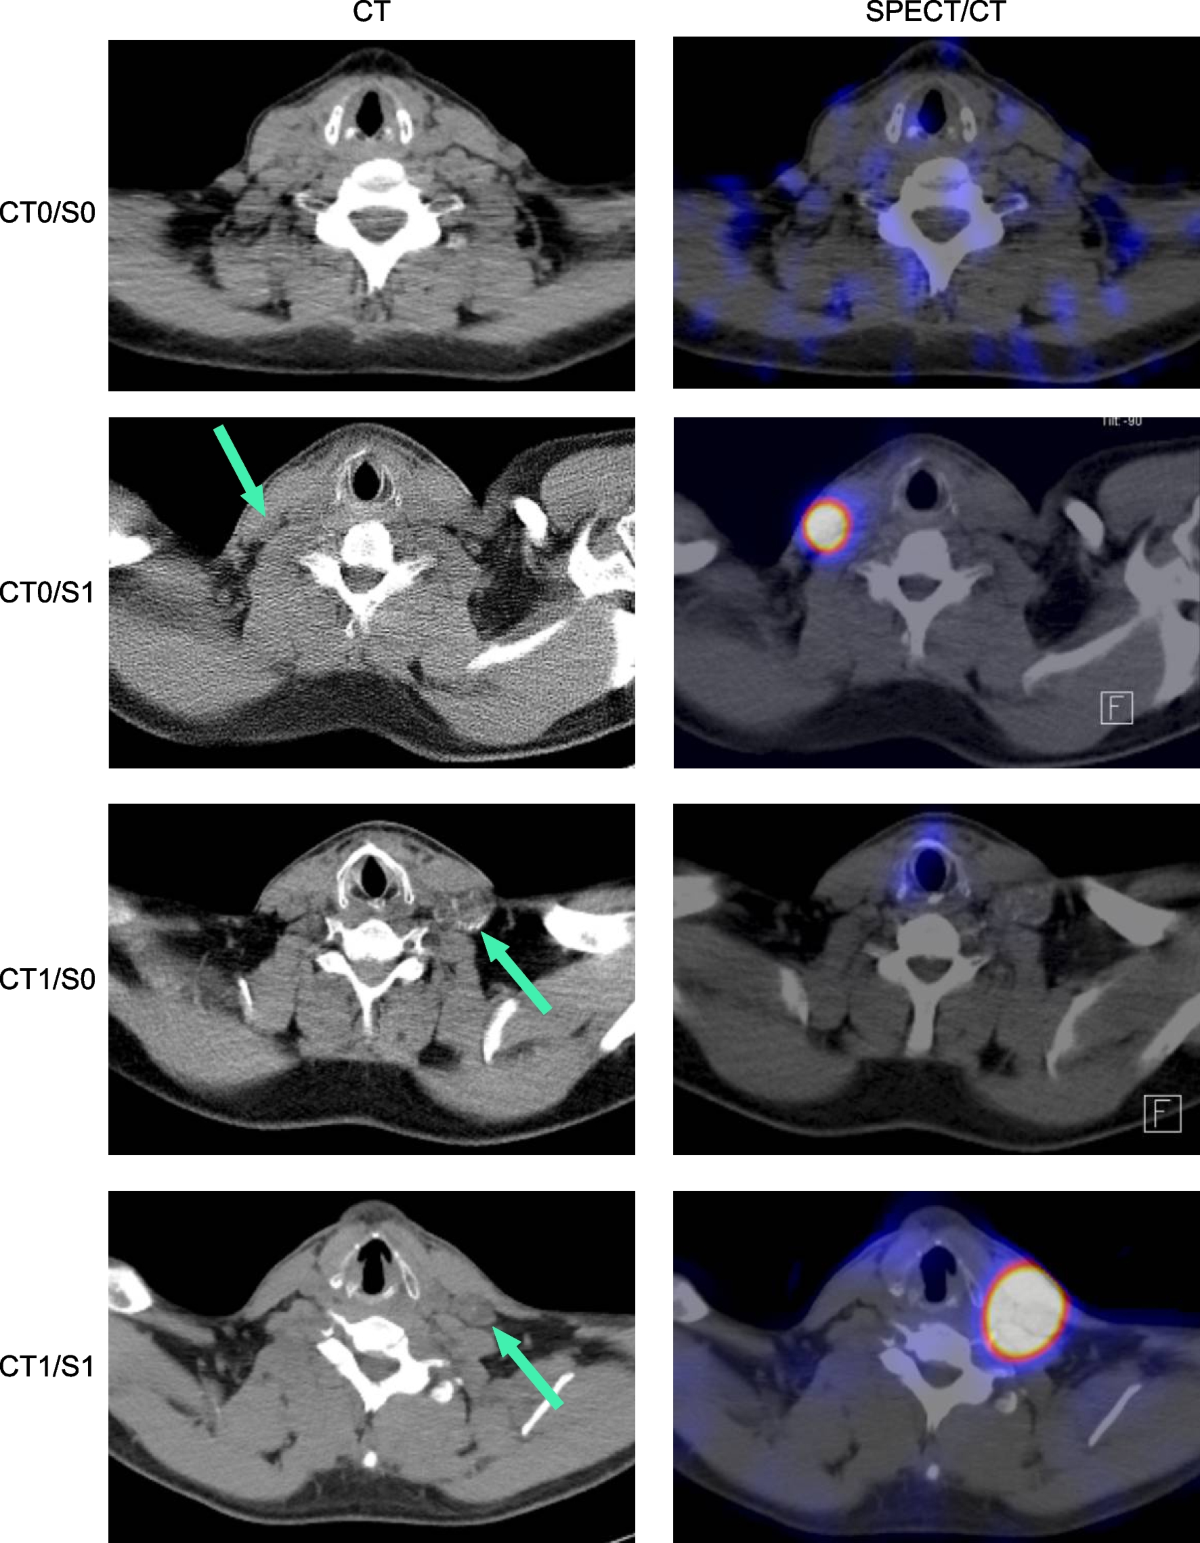

- 根據 CT(增大≥1 cm,小<1 cm)和 131I 攝取(陽性或陰性)對 LNM 進行分類。

- 根據大小(<1 cm, ≥1 cm)和 131I 攝取對 LNM 進行分類。